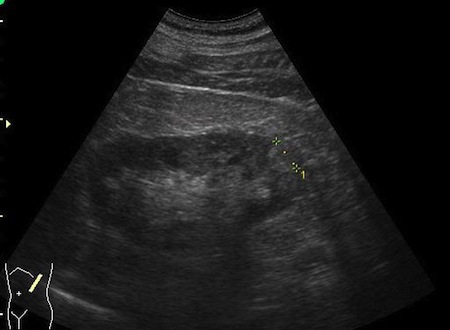

Guzy nerek o typie angiomyolipoma wykrywane są najczęściej przypadkowo w czasie badania USG jamy brzusznej , tomografii komputerowej lub rezonansu magnetycznego. W badaniu USG jamy brzusznej guzy o typie angiomyolipoma widoczne są jako hiperechogenne guzy i większości przypadków nie stwarzają problemu diagnostycznego.

Fot. Angiomyolipoma średnicy 1,cm w dolnym biegunie prawej nerki